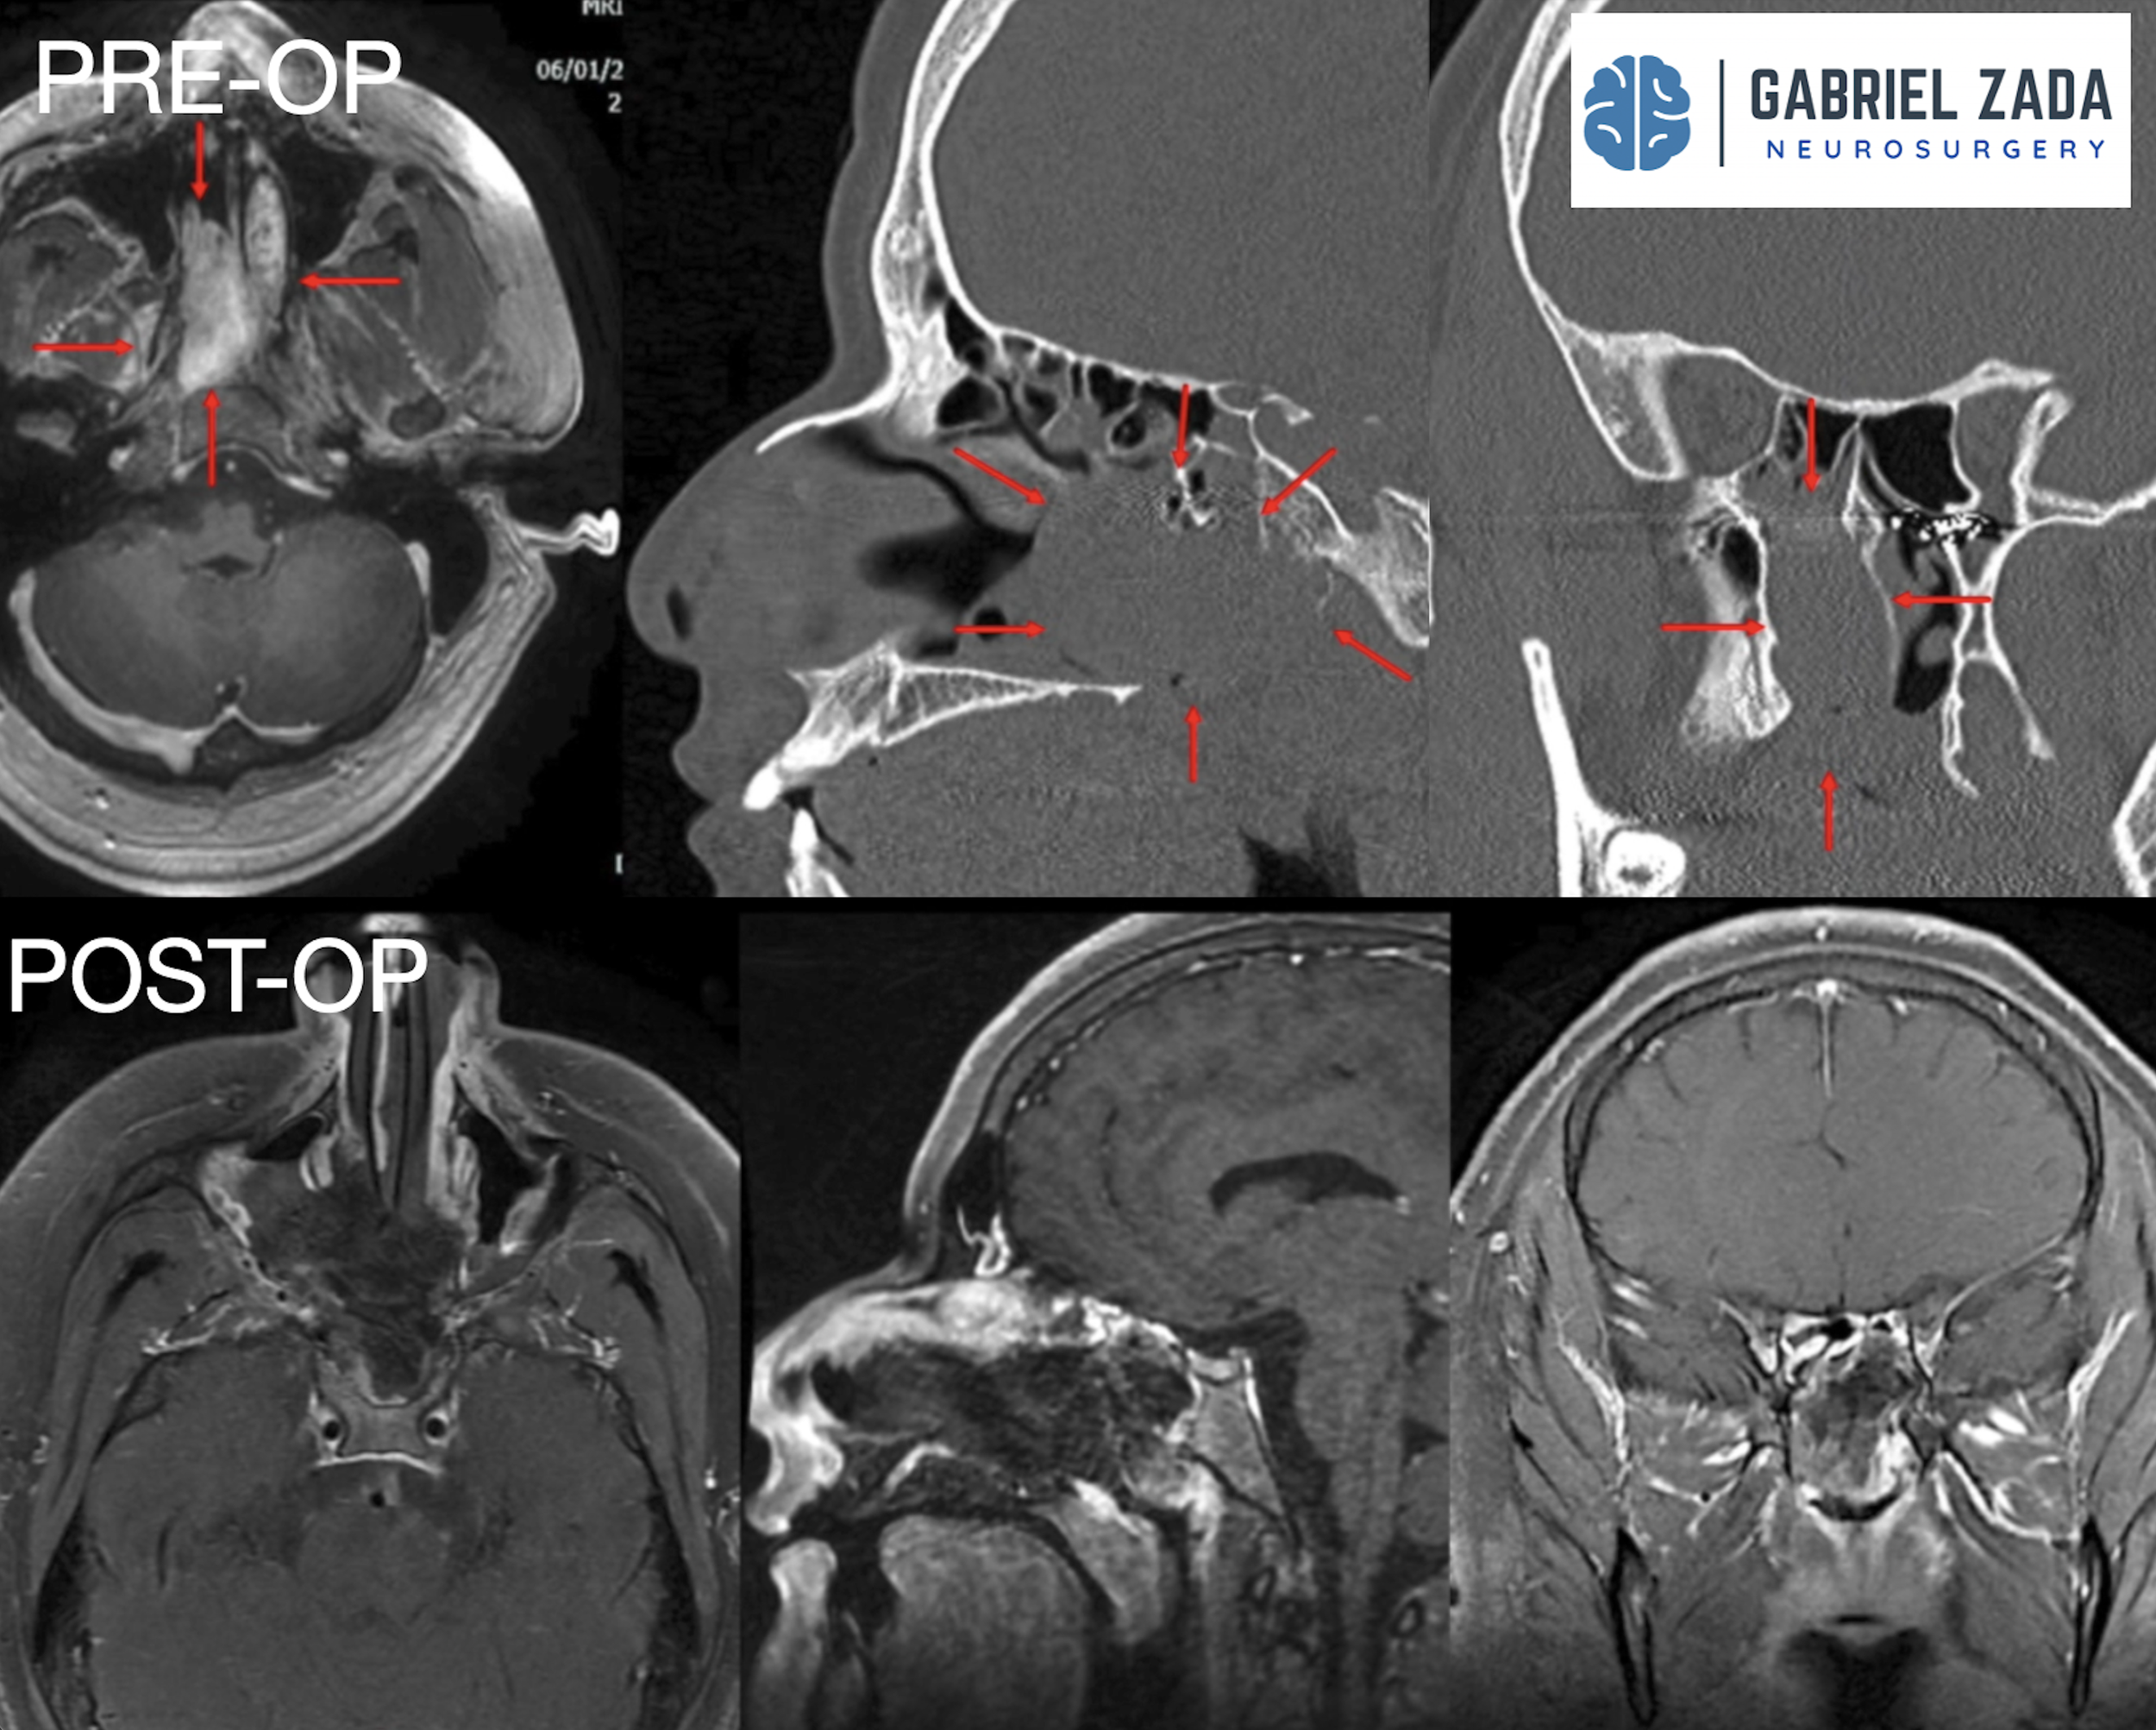

Explore this comprehensive gallery featuring pre‑ and post‑operative imaging of patients with skull‑base tumors treated by Gabriel Zada, MD, MS, FAANS, FACS. These cases highlight Dr. Zada’s expertise in advanced neurosurgical techniques and outcomes.

*Representative cases shown for educational purposes. All images de-identified. Individual results vary.